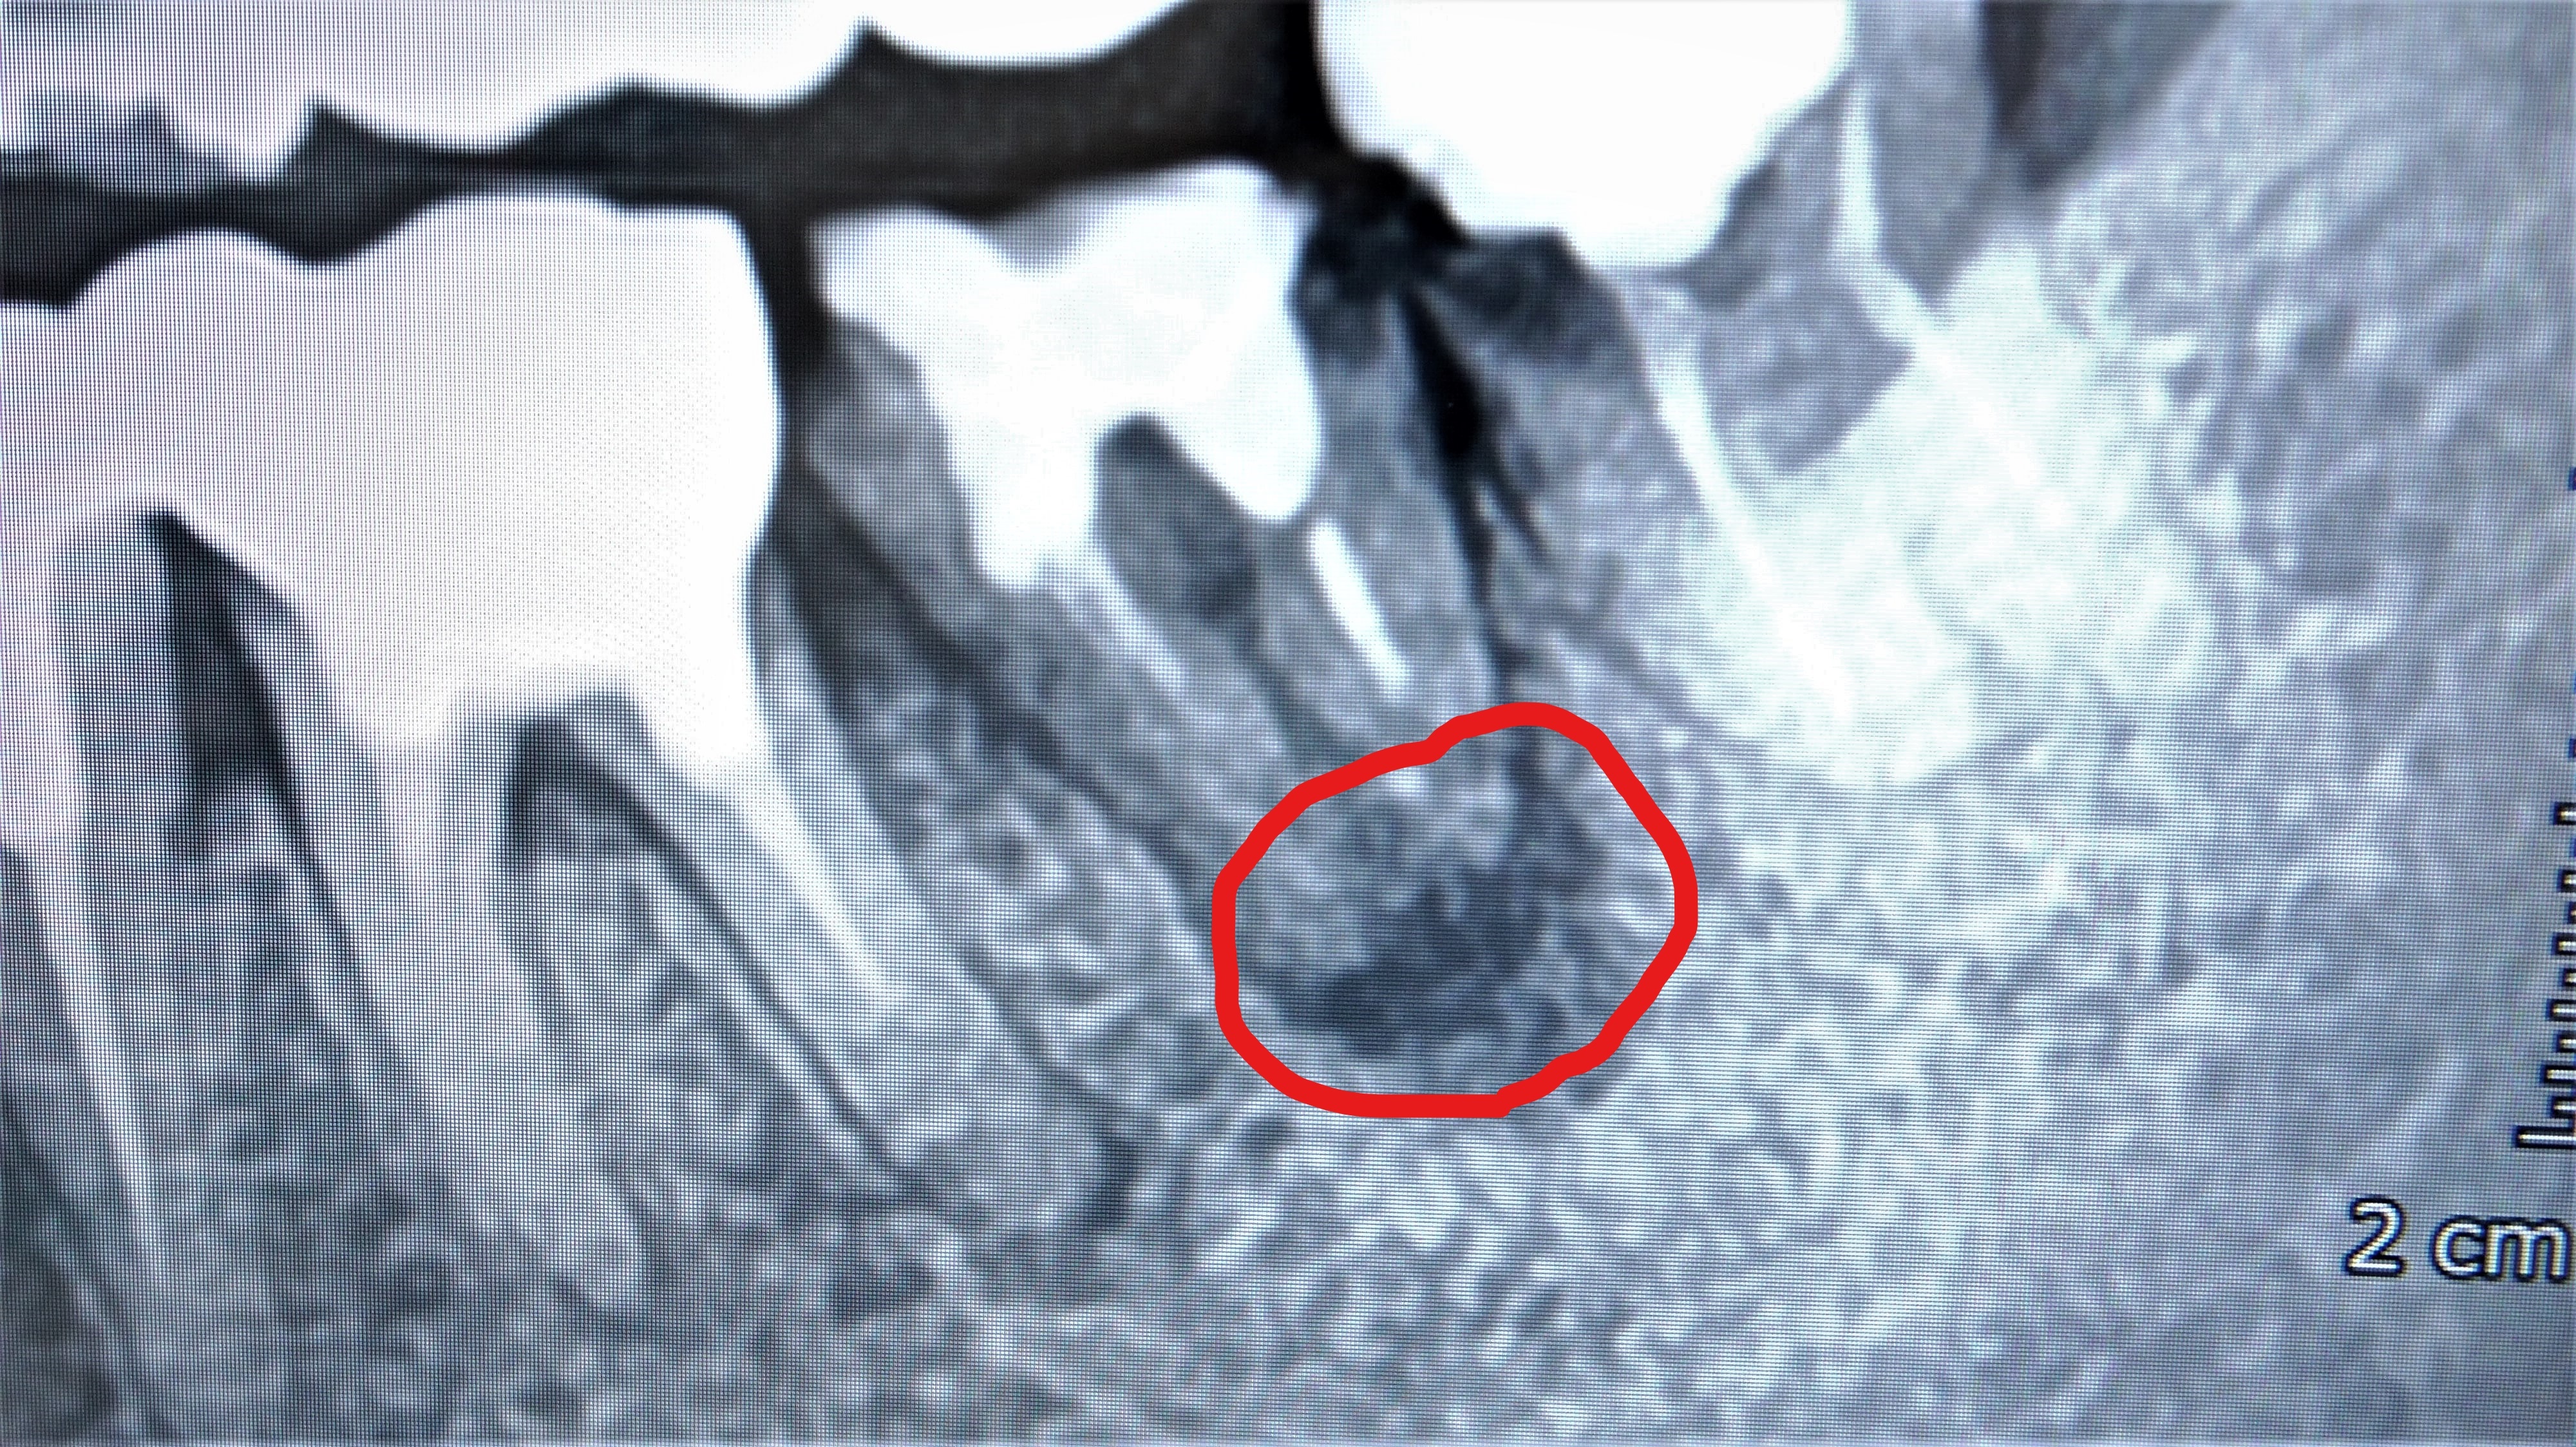

根管治療後に根管の中の薬が根の先まで入っていないため、根管の中で菌が増殖し

根尖に化膿性の炎症が生じている写真です。

黒く写っている病巣が急性化すると歯茎が腫れて強い痛みがでます。